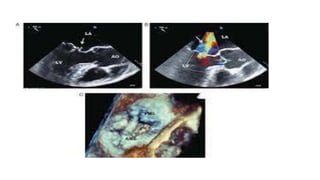

PROSTHETIC VALVE ENDOCARDITIS

• Prosthetic valve dehiscence is highly suggestive of IE.

• Dehiscence can be the only manifestation of IE with a prosthetic

valve in the absence of vegetation or abscess

• A valve rocking motion may indicate valve dehiscence.

• Paravalvular regurgitation may also indicate prosthetic valve

endocarditis but should be compared with any prior paravalvular

regurgitation

• TEE solves this problem for mitral prostheses and improves it for

aortic prostheses .However, when both mitral and aortic prostheses

are present, the mitral device tends to obscure the aortic valve.

Tricuspid and pulmonic devices pose similar problems.

Echocardiographic image ofinfective endocarditis over the pulmonary valve